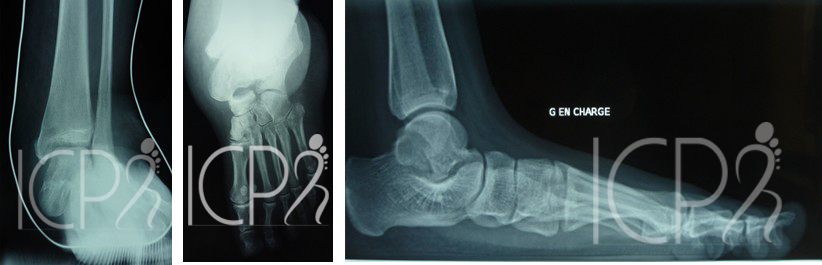

Bilan radiographique

Les radiographies en charge (debout) permettent de quantifier les déformations et de suivre leur évolution. L’échographie ou l’IRM recherchent une tendinopathie ou rupture du tendon tibial postérieur (tendon soutenant la voûte plantaire). Un scanner avec une scintigraphie permet également de rechercher une atteinte articulaire associée (arthrose).